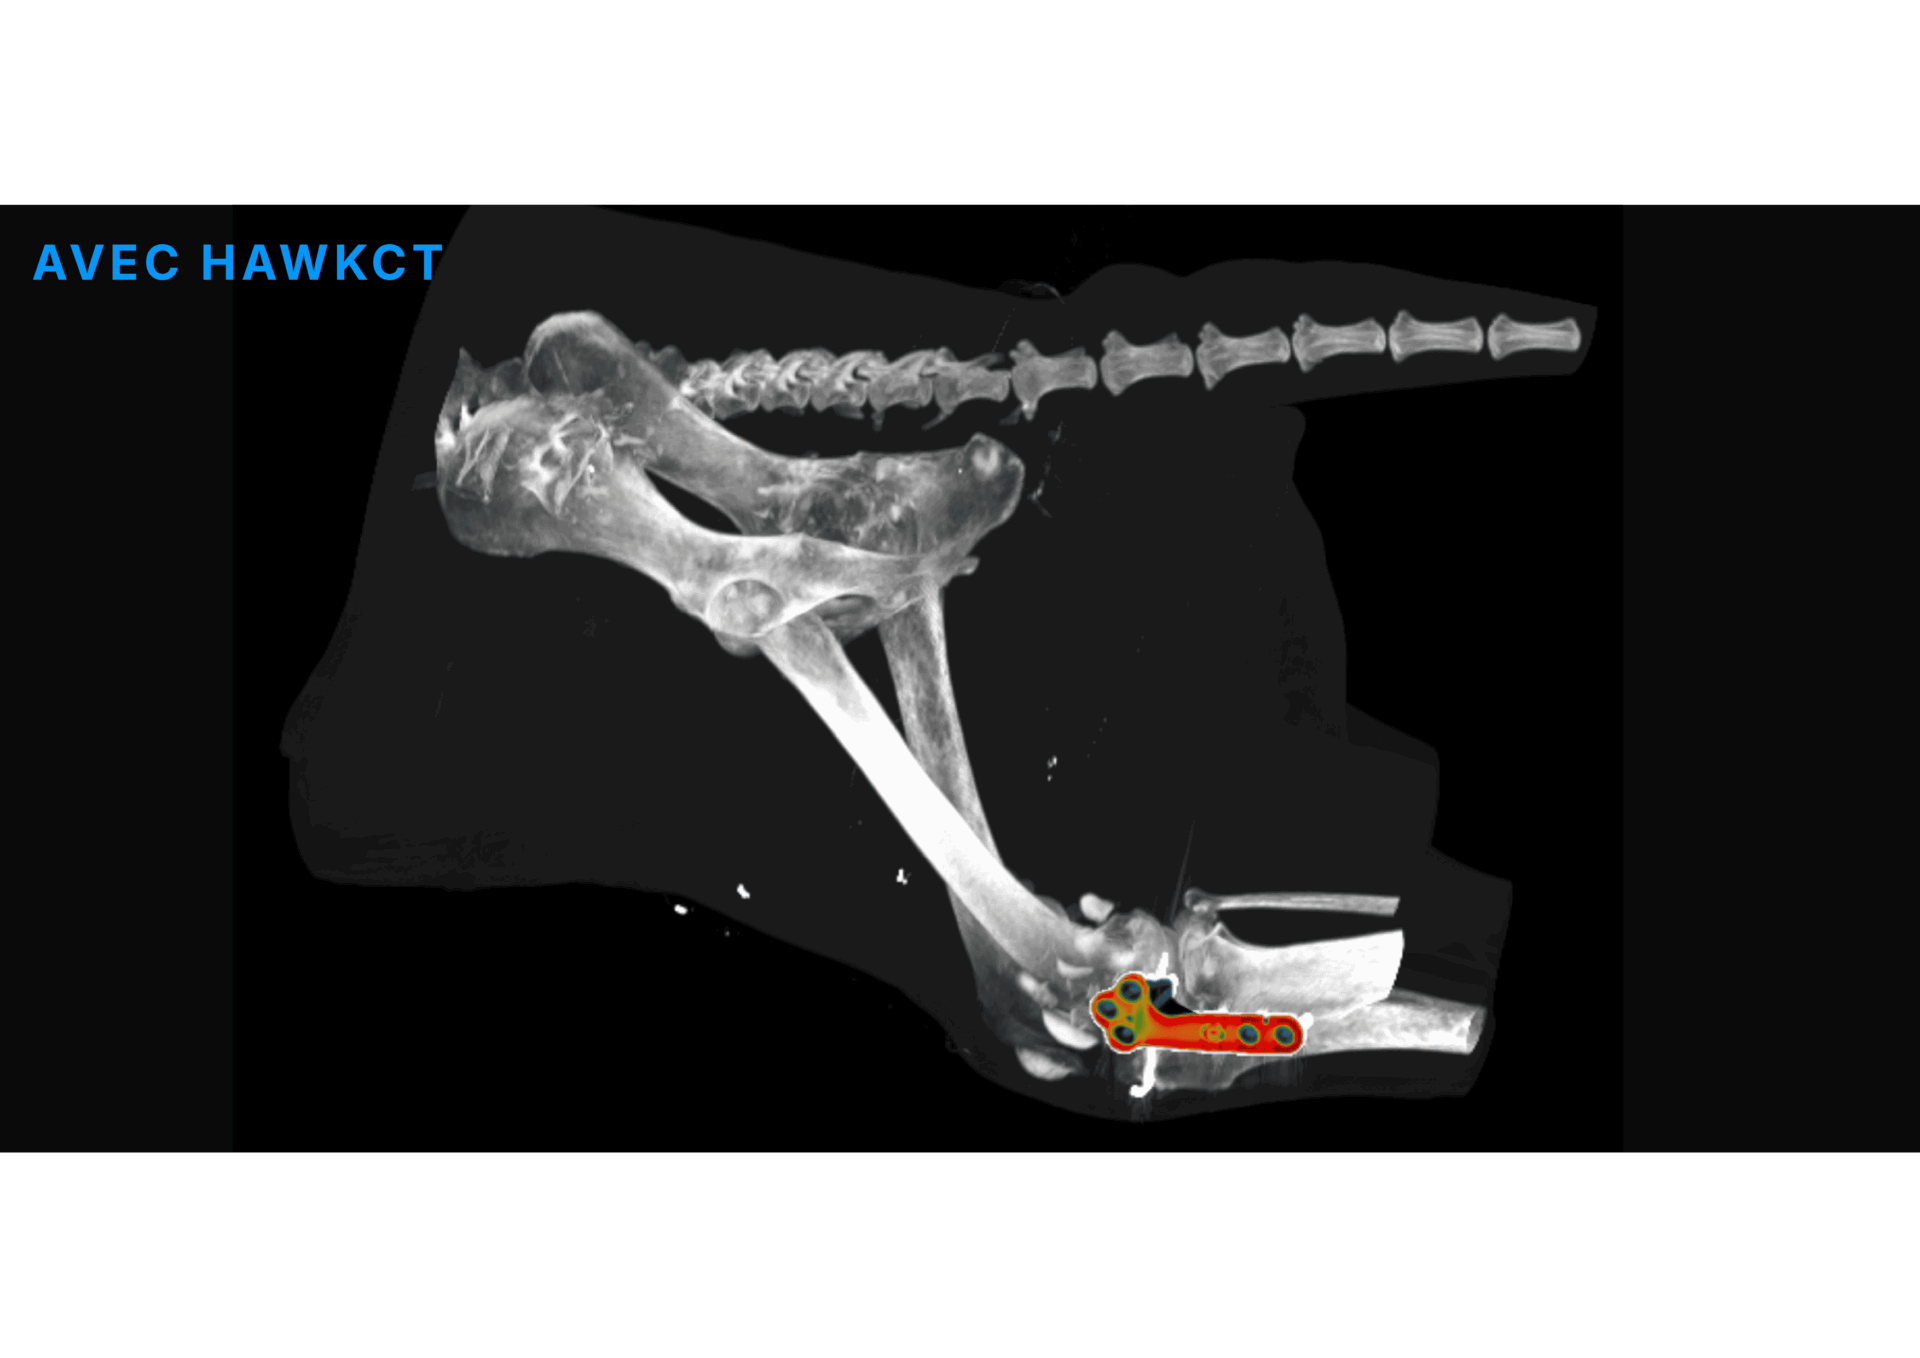

HawkCT est un algorithme de deep learning appliqué au scanner vétérinaire, conçu pour définir un nouveau standard en imagerie. Il offre des examens plus rapides, une réduction de l’exposition aux radiations et une meilleure qualité d’image.

Sa reconstruction avancée renforce le contraste et la résolution, garantissant une qualité d’image constante sur toutes les séquences. Exclusivement conçu pour les vétérinaires, entraîné et validé sur des données animales, HawkCT permet aux cliniques d’accéder à une imagerie scanner plus rapide, plus sûre et plus durable.